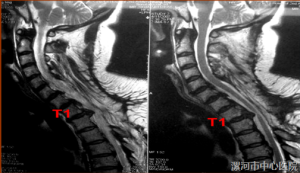

50分钟生命时速:漯医骨科首创"先解压后复位"改写颈椎...

05/15